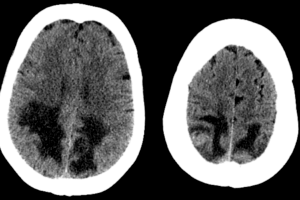

Case: PRES or mets?

Case history: 55 year old female with history of lung adenocarcinoma presents with difficulty seeing. She was treated with carboplatin and paclitaxil two months prior to admission. CT head showed hypodensities in... Read more »